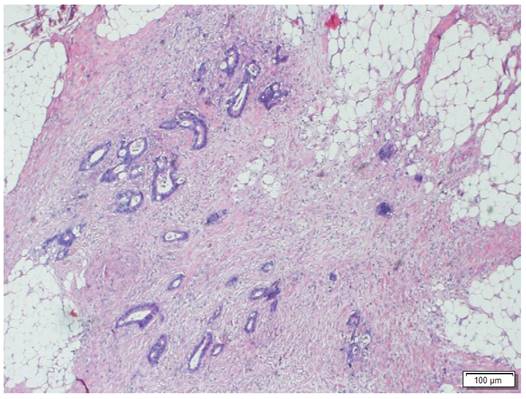

Morphologic image of a Tumor Deposit. Neoplastic cells infiltrating pericolic adipose tissue. Hematoxylin and Eosin staining, 40 X.

TDs were detected in 178 patients (12.5%) (Figure 2). Of these, 60 (33.7%) had tumors that did not present LNM, while in 118 (66.3%) the TD coexisted with LNM. The incidence of TD increased as the number of LNMs increased (6.1% in LNM-negative tumors, 18.8% in tumors with 1-3 LNMs and 51.3% in tumors with > 3 LNMs; p < 0.001).